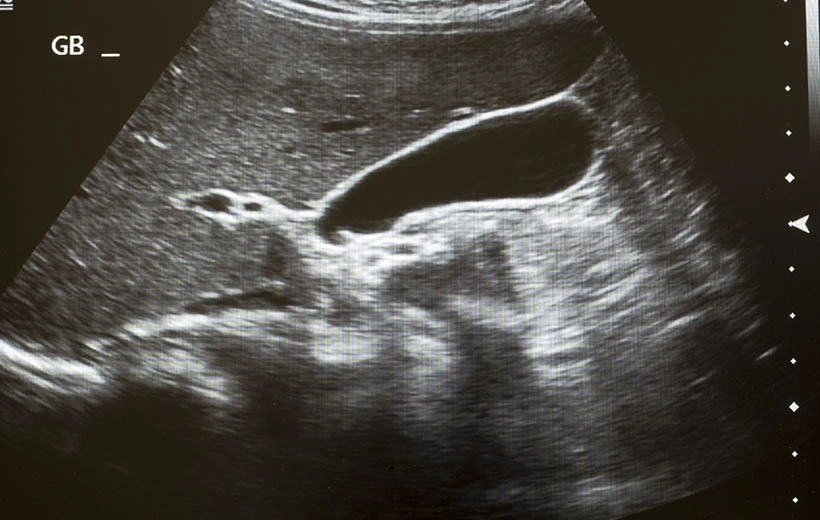

- инструментальные исследования, которые могут с высокой точностью определить гибель эмбриона. УЗИ вагинальным датчиком при анэмбрионии показывает, что объем пустого плодного яйца более 2,5 см. При повторном обследовании спустя 2 недели, не фиксирующем биение сердца, ставят данный диагноз.